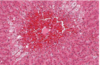

Nutmeg Liver

Appearance of the parenchyma with animal suffering from chronic hepatic congestion